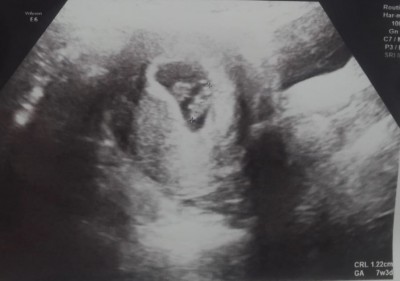

Merhaba 7+5 aceba ikizmi

Gebelik haftası 7+5

Dr yorum yapmadımi kese iki tane gibi

Doktor beslenme kesesi dedi ama görenler ikiz gibi diyor

2 tane gibi görünüyor ama doktor demedimi bişey uzak bıraz net secemedım canım

Beslenme kesesi dedi ama ben emin olamadım 7 haftalikta böyle kese gözükür mü

Bence tek yumurta ikizi :) başka doktora da git canim

Ben e orda çift yumurta ikizi gibi bizde niue tek görüldü bence ikiz

Aynı kesede iki tane embriyo var :) Doktora gidince net belli olur ama buna göre hiç yorum yapmadı mı canım? Hayırlı olsun bu arada

Tek yumurta ikizi bunlar :) ne guzel sağlıkla kavuşun

asiri ikize benziyoru 7. haftamda gittigimde benimki boyle gozukmuyordu gerci benimki 4 gun geriden geliyor bak kesin ikizdir :)

Canm çift yumurta ikizi değil zaten ikiz hamile olduğum için biliyorum tek yumurta ikizi midir bilemem ama doktorun beslenme kesesi dediği yolk kesesi galiba öyle bir durum oluyor hatta 12.haftalarda kendiliğinden yok oluyor netten araştır tam anlarsın

Bence yolk kesesi zaten haftası 8 haftalık kalp atışı da duyulmuş ikiz olsa doktor bilir

bildiğin iki tane bu canım bizimkilerde böyle iki tane birsey yoktu

kesinlikle başka doktora git tek yumurta ikizi gibi

yolk kesesi denilen şeymi acaba :) ama bence ikiz durmuyor